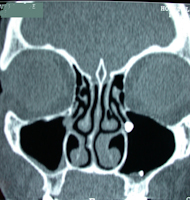

TRAITEMENT D'UNE SINUSITE ASSOCIEE

Il peuvent coexister aux troubles ventilatoires notamment une sinusite chronique ou une tendance aux sinusites aiguës répétées, elle peuvent alors être traitée dans le même temps par une méatotomie c'est-à-dire un agrandissement de l'orifice naturel du sinus maxillaire dans la fosse nasale. Seuls les sinusites majeurs où les polyposes nasales justifient une intervention chirurgicale en deux temps.

Pour toutes ces interventions il s'agit de microchirurgie endoscopique sans cicatrice et sans oedème extérieur ajouté.  Le scanner pré-opératoire est un élément radiologique indispensable avant ce type d'intervention.

Anomalie anatomique appelée

concha bullosa du cornet moyen gauche